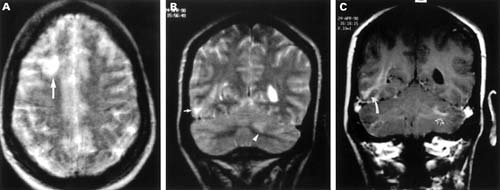

Matias G, Canas N, Antunes I, Vale J. đang làm việc tại khoa thần kinh, bệnh viện Egas Moniz, Lisboa Med Port vào năm 2008 công bố về hội chứng này có đề cập: các triệu chứng thần kinh trên sốt rét thường có liên quan nhiễm trùng nặng do Plasmodium falciparum. Ít gặp hơn, suy giảm ý thức, động kinh và khuyết tật về thị giác cũng như thính giác là có liên quan đến hạ đường huyết (do sốt rét hoặc do thuốc quinine) hoặc độc tính của thuốc. Trong những năm trước đây, nó được nhận ra là một biến chứng thần kinh hiếm sau khi điều trị sốt rét do Plasmodium falciparum - Hội chứng PMNS. PMNS xảy ra từ vài ngày đến vài tuần sau khi đã làm sạch ký sinh trùng, biểu hiện bởi một hội chứng hay bệnh lý não với độ trầm trọng khác nhau. Cơ chế bệnh sinh liên quan đến PMNS vẫn chưa được hiểu thấu đáo, có thể nghĩ đến do nguyên do miễn dịch. Ca bệnh báo cáo ở đây là một đàn ông 61 tuổi có biểu hiện bệnh lý não nghiêm trọng (cơn mê sảng, thất điều tiểu não và ophthalmoparesis), 2 ngày sau khi hồi phục hoàn toàn sốt rét Plasmodium falciparum. Xét nghiệm máu ngoại vi lặp lại âm tính. Chụp MRI trong pha cấp chỉ ra có những bất thường chất trắng đa ổ lan tỏa. Bệnh nhân được điều trị bằng thuốc methylprednisolone liều cao đã giải quyết các khiếm khuyết thần kinh hoàn toàn. Sau 9 tháng chụp lại MRI chỉ thấy các tổn thương tồn lưu rất bé.

Hội chứng PMNS: Một ca bệnh viêm não tủy lan tỏa cấp tính?

Nhóm tác giả A H Mohsen, M W Mckendrick, M L Schmid, S T Green đang công tác tại khoa truyền nhiễm và y học nhiệt đới, Bệnh viện hoàng gia Hallamshire, Sheffield, Anh và khoa Thần kinh lâm sàng, khoa chẩn đoán hình ảnh về thần kinh báo cáo bệnh nhân nữ 30 tuổi với rối loạn thần kinh 8 tuần sau khi hồi phục hoàn toàn từ sốt rét Plasmodium falciparum. Chụp MRI trong lúc bị bệnh cho thấy các hình ảnh bất thường các chất trắng đa ổ (multifocal white matter abnormalities). Cô ta hồi phục hoàn toàn mà không cần bất cứ điều trị đặc hiệu nào. Chụp MRI lặp lại 6 tháng sau đó cho thấy tất cả thương tổn đã được giải quyết. Mặc dù thuật ngữ của hội chứng PMNS đã được dùng để mô tả những ca như thế, song hình ảnh lâm sàng và các chỉ số cận lâm sàng không thể phân biệt được với các bệnh lý viêm não tủy lan tỏa cấp tính (acute disseminated encephalomyelitis).